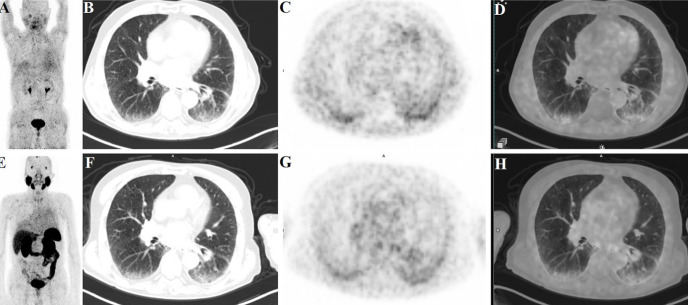

We present the 68Ga-prostate-specific membrane antigen (PSMA) and 68Ga-fibroblast activation protein inhibitor (FAPI)-04 positron emission tomography/computed tomography (PET/CT) findings comparatively of a 76-year-old man with a history of progressive dyspnea and evidence of interstitial lung disease (ILD) abnormalities on high-resolution CT. Moderate PSMA uptake was observed in areas with ILD abnormalities on 68Ga-PSMA PET/CT. 68Ga-FAPI-04 PET/CT showed relatively higher FAPI-04 uptake in these regions. These findings offer the potential to assess disease activity at the cellular and molecular levels. This approach may provide valuable insight into the pathophysiology of ILD beyond the structural changes captured by traditional imaging methods.